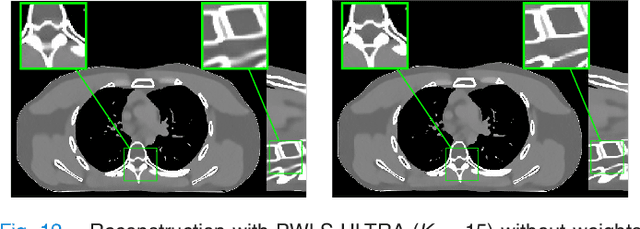

Abstract:The development of computed tomography (CT) image reconstruction methods that significantly reduce patient radiation exposure while maintaining high image quality is an important area of research in low-dose CT (LDCT) imaging. We propose a new penalized weighted least squares (PWLS) reconstruction method that exploits regularization based on an efficient Union of Learned TRAnsforms (PWLS-ULTRA). The union of square transforms is pre-learned from numerous image patches extracted from a dataset of CT images or volumes. The proposed PWLS-based cost function is optimized by alternating between a CT image reconstruction step, and a sparse coding and clustering step. The CT image reconstruction step is accelerated by a relaxed linearized augmented Lagrangian method with ordered-subsets that reduces the number of forward and back projections. Simulations with 2-D and 3-D axial CT scans of the extended cardiac-torso phantom and 3D helical chest and abdomen scans show that for both normal-dose and low-dose levels, the proposed method significantly improves the quality of reconstructed images compared to PWLS reconstruction with a nonadaptive edge-preserving regularizer (PWLS-EP). PWLS with regularization based on a union of learned transforms leads to better image reconstructions than using a single learned square transform. We also incorporate patch-based weights in PWLS-ULTRA that enhance image quality and help improve image resolution uniformity. The proposed approach achieves comparable or better image quality compared to learned overcomplete synthesis dictionaries, but importantly, is much faster (computationally more efficient).